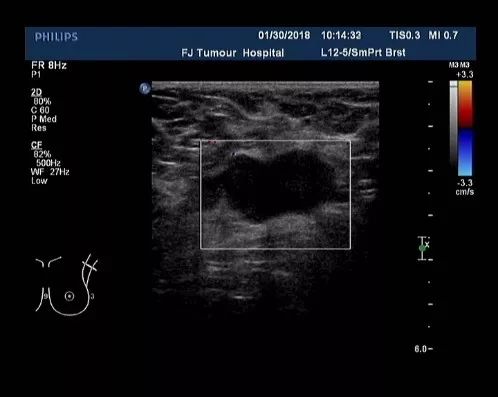

▎疗效评估:B超(2018-07):左乳2-3点处探及一低回声区,大小约2.2cm×1.4cm,边缘不规则,可见成角、毛刺,内部回声不均;左腋中、下组探及数个低回声,大者约1.6cm×0.7cm(腋中组)、0.9cm×0.5cm(腋下组),边界尚清,类圆形,皮髓质分界不清,皮质不规则增厚,淋巴结门消失,右乳及右腋窝未见异常。